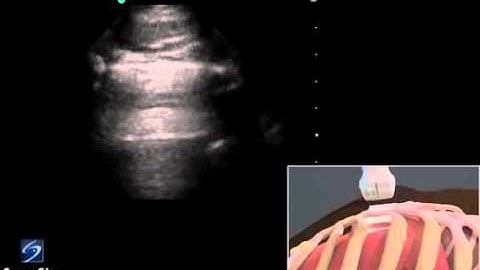

3D How To Lung Sliding Detection with Phased Array Transducer